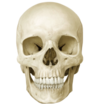

5

Q

A

Norma frontalis/fronal aspect